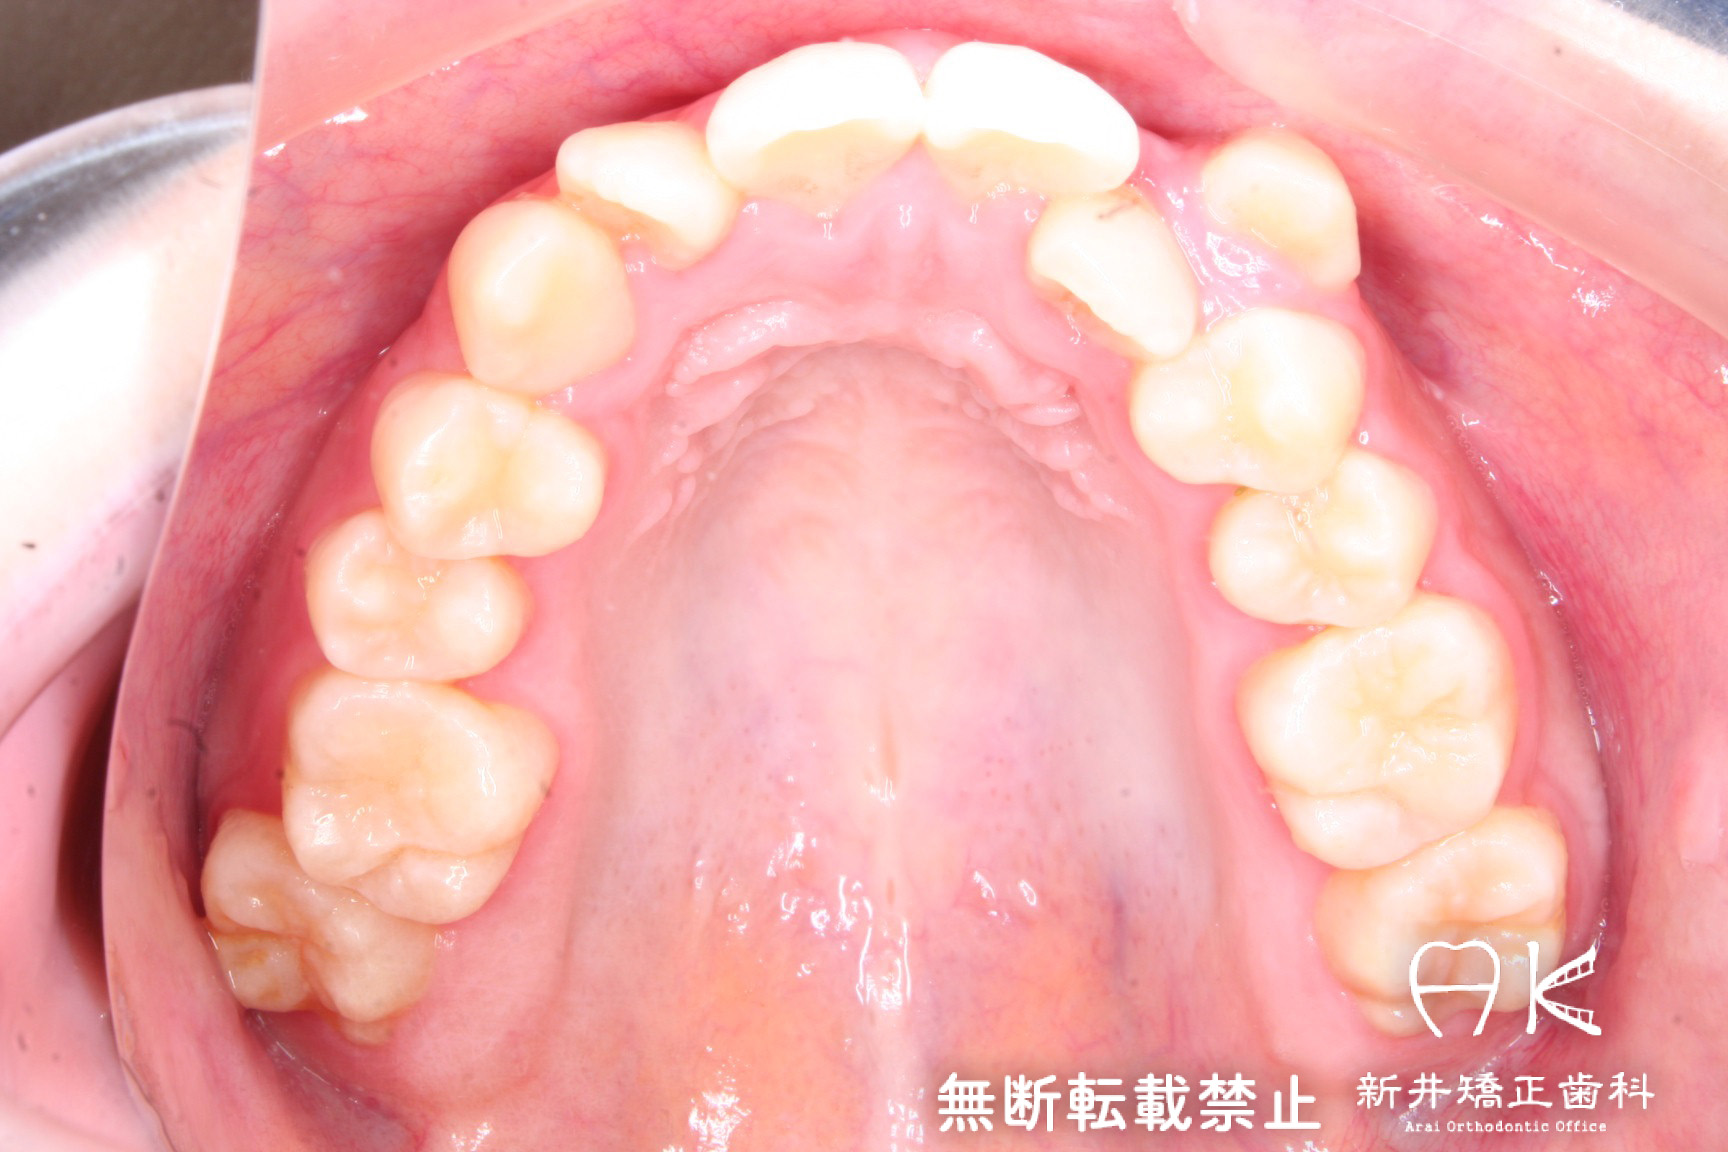

叢生(ガチャ歯・八重歯)と正中のずれの治療

| 症状・診断名 | 叢生 |

| 治療前 | 八重歯や歯のデコボコ、前歯の正中のずれが大きい患者さんでした。 上下顎両側第一小臼歯(前から4番目の歯)を抜歯して治療を行いました。 |